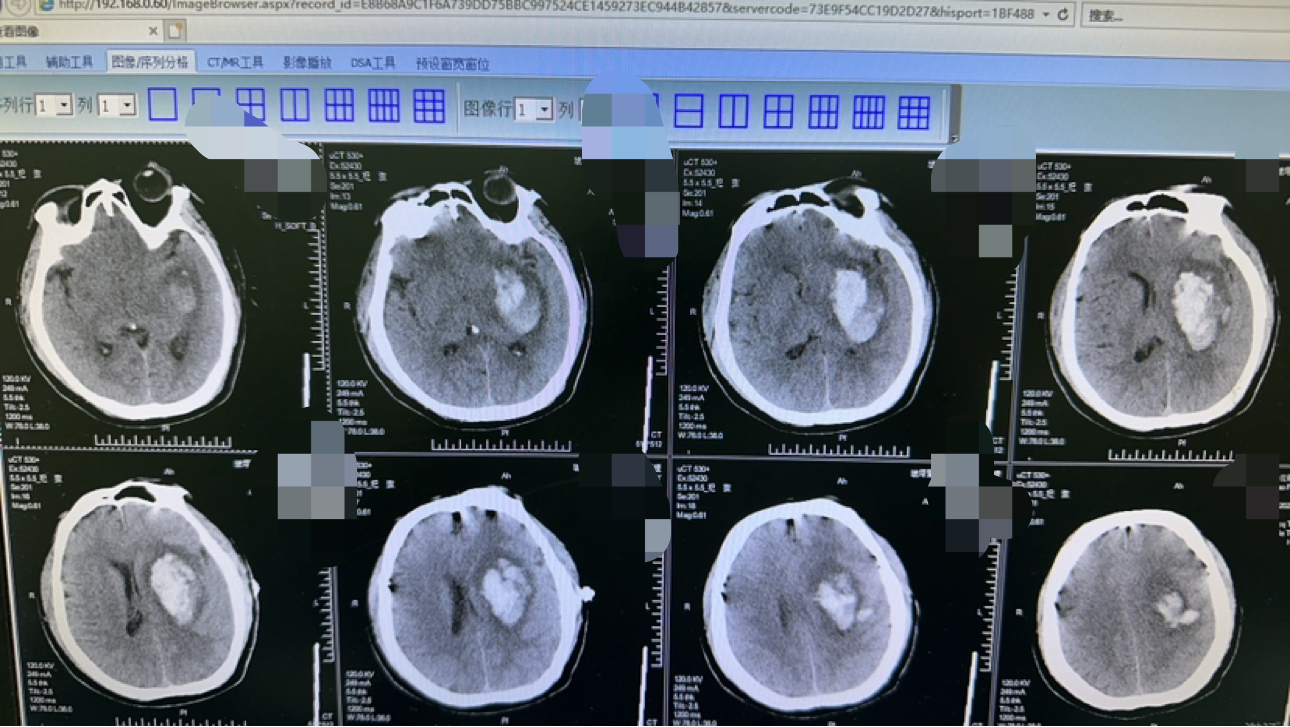

毫米级精度:机器人系统实现亚毫米级血肿定位,减少脑组织损伤。

极速微创手术:0.5cm切口,0.3cm骨孔,10分钟手术,2ml出血量。